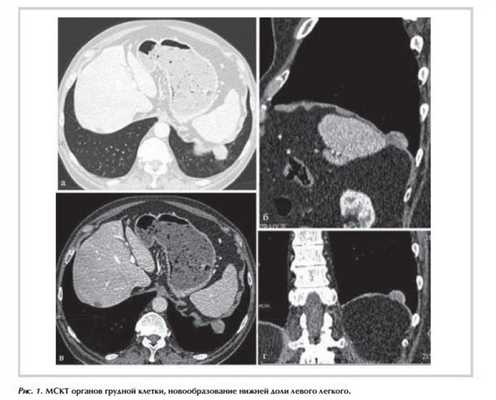

Пациент Ц., 78 лет, обратился в Институт хирургии им. А.В. Вишневского с жалобами на постоянный сухой кашель, который появился около года назад. При рентгенографии органов грудной клетки выявлена очаговая тень в проекции нижней доли левого легкого. При компьютерной томографии (КТ) органов грудной клетки визуализировано новообразование в проекции нижней доли левого легкого с четкими ровными контурами размером 3,8×1,9×3,4 см, интенсивно накапливающее контрастный препарат (рис. 1 ). При обследовании в объеме мультиспиральной компьютерной томографии (МСКТ) брюшной полости и малого таза, ультразвукового исследования (УЗИ) щитовидной железы, сцинтиграфии костей скелета очаговых новообразований в других органах выявлено не было. Учитывая гиперваскулярный характер новообразования, невозможность исключить первичную принадлежность опухоли к диафрагме, отсутствие возможности его трансторакальной биопсии пациенту выполнена эксцизионная биопсия опухоли.